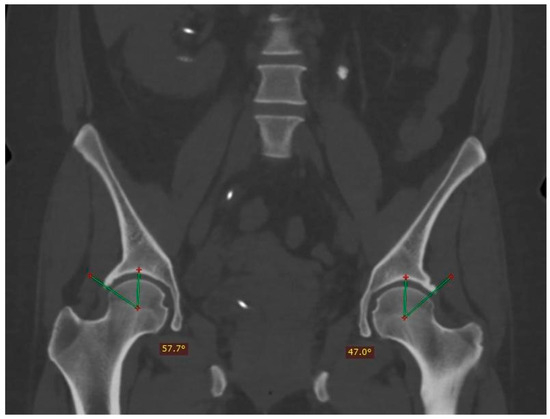

The Kolmogorov–Smirnoff test confirmed the normal distribution of data (p = 0.084). Regarding the interpretation of the mean comparison test, the p-values of the variables right Wiberg angle, left Wiberg angle, right excrescence, left excrescence, pincer, and cam suggested significant differences in the frequency of pincer-type FAI among the height groups (Table 1), where the compressing type with alpha angle was more common than non-compressing (Figure 4 depicts the measurement of the Alpha angle).

Figure 4.

Measurement of the Alpha angle in a patient with femoroacetabular cam impingement. The angle is obtained from the start of the middle femoral head by means of a linear stroke that runs through the center of the femoral neck and another to the point where the sphericity is lost at the junction between the head and the neck. The normal value is equal to or less than 50°.